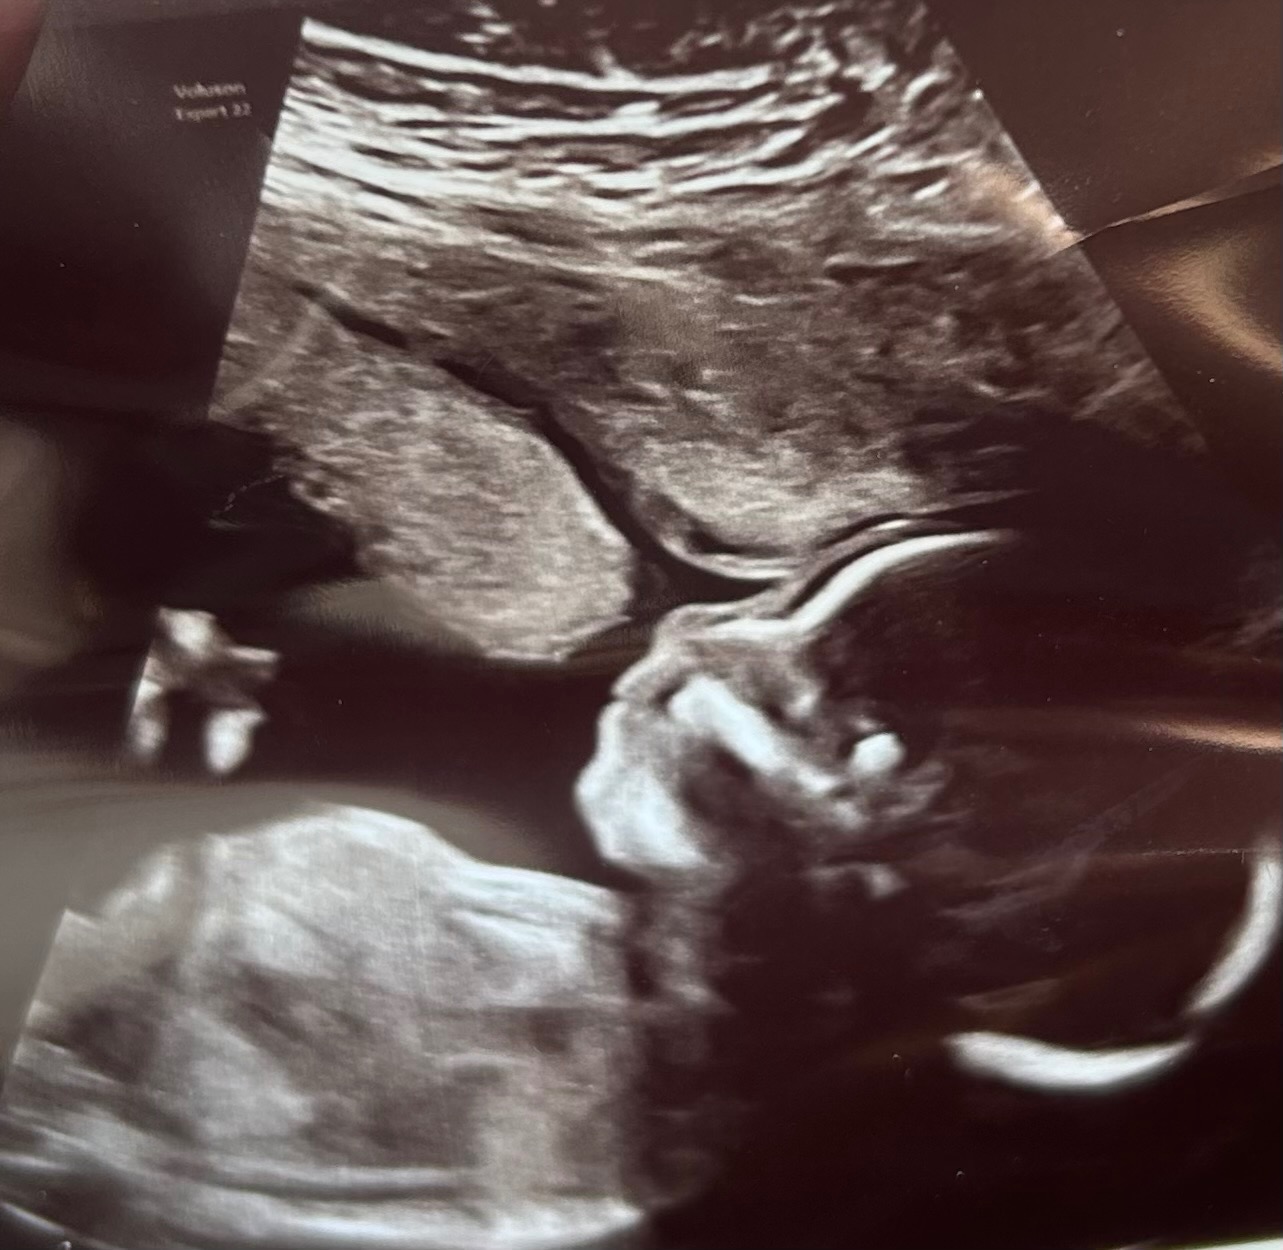

As some of you know, we found out our precious baby Skylar was diagnosed with Down Syndrome, Trisomy 21, at our 23-week scan.

Shortly after her DS diagnosis, we were told that she will need surgery immediately following her birth to address a serious medical condition called Duodenal Atresia. She will be placed in the NICU after birth and will remain there until she has completely healed, which generally takes 3-4 weeks.